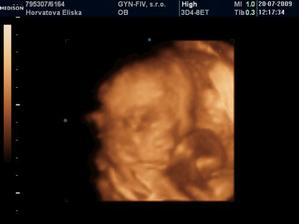

Dvojicky po KET

tak sme sa dockali-nase dvojicky sa narodili v 37+1 tt -20.10.09 cisarskym rezom -11:00 Matúško 3150g a 48cm a 11:02 Natálka 3030g 48cm,